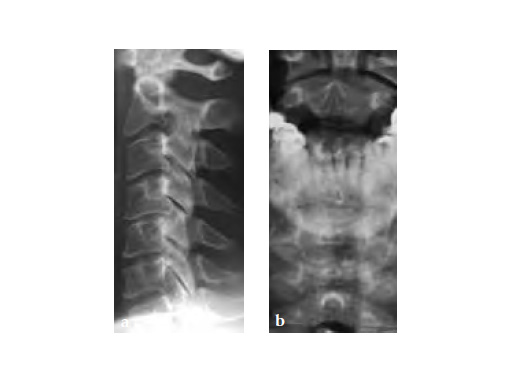

59-year-old female with neck pain and right radicular arm pain C5 and C6 and weakness during walking. An MRI was performed and a severe DDD with soft spinal stenosis C3C6 was diagnosed. Neurophysiology revealed myelopathic spinal cord changes. Decompression and stabilization C3/4, C4/5, and C5/6 using Zero-P was performed. After surgery the patient was nearly free of pain, had no complains regarding dysphagia, and was neurologically improved.